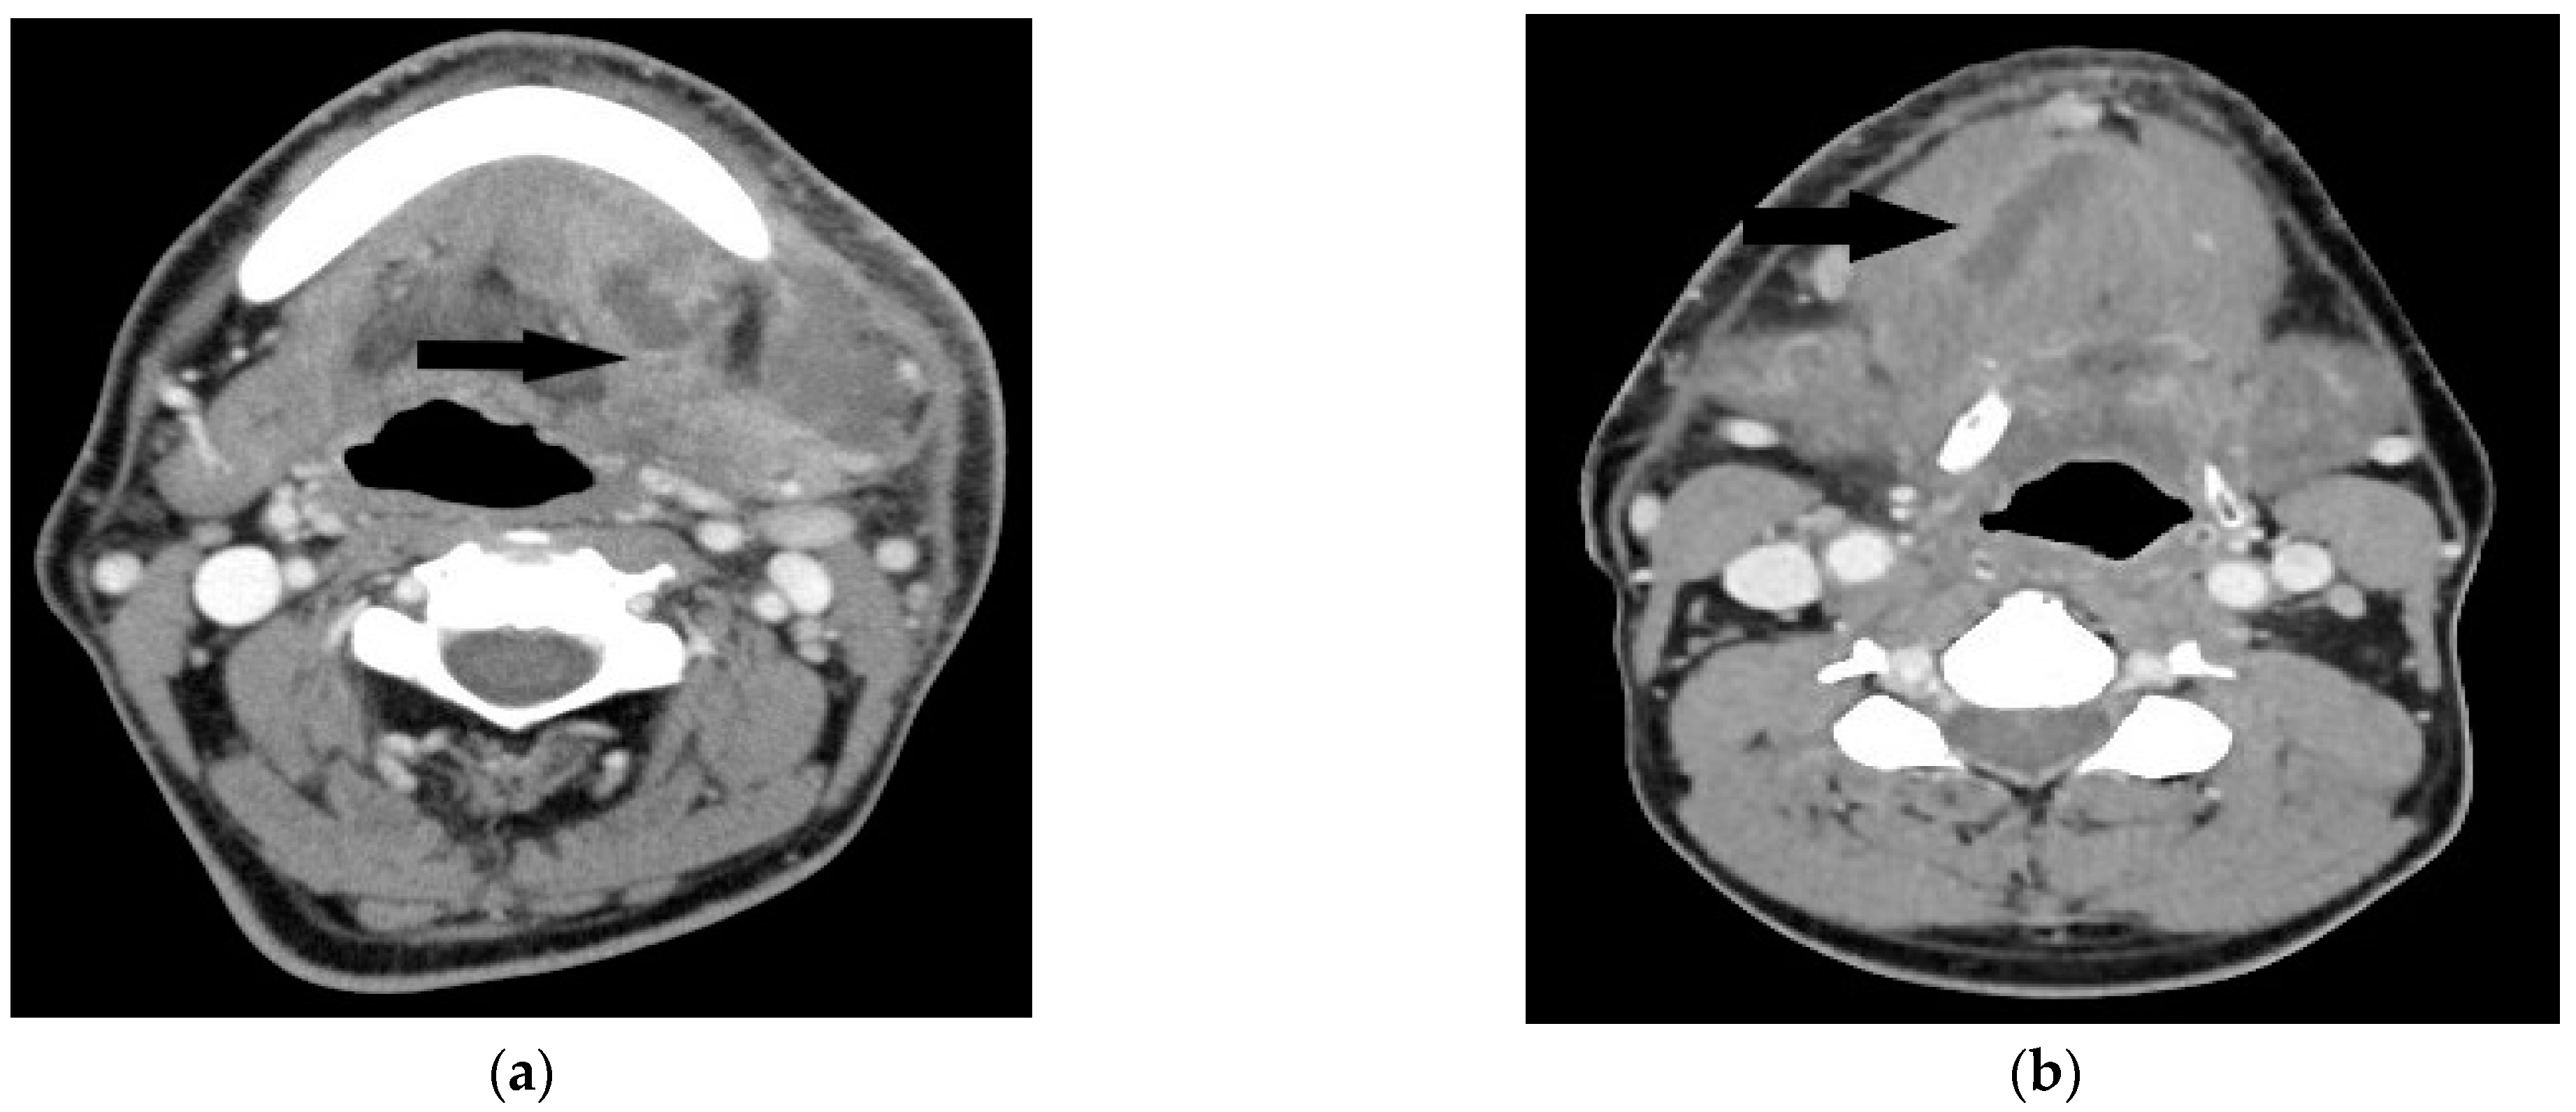

- Scaglione, M.; Pinto, A.; Giovine, S.; Di-Nuzzo, L.; Giuliano, V.; Romano, L. CT features of descending necrotizing mediastinitis--a pictorial essay. Emerg. Radiol. 2007, 14, 77–81. [Google Scholar] [CrossRef]